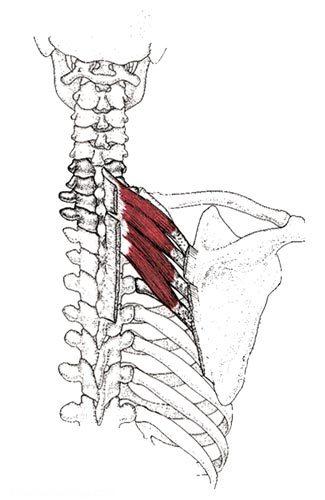

عضله متوازی الاضلاع

این عضله در اصل دو عضله است که شباهت زیادی در نحوه قرار گیری و عمل دارند. عضله متوازی الاضلاع بزرگ از روی خارهای مهره های دوم تا پنجم پشتی شروع می شود و به بخش تحتانی لبه داخلی استخوان کتف متصل می شود. جهت کشیدگی تارهای این عضله مایل است. عضله متوازی الاضلاع کوچک نیز از روی انتهای تحتانی رباط نوکه در پشت گردن و خارهای مهره های هفتم گردن و اول پشتی شروع شده و به ریشه خار استخوان کتف متصل می شود، تارهای این دو عضله به موازات هم قرار دارند.